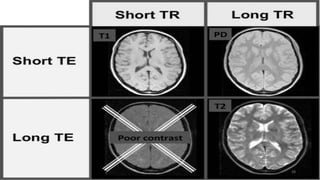

What is a Sequence?

• Sequence of events in MRI

machine

• By varying the sequence of RF

pulses applied & collected,

different types of images are

created

Playing with TR and TE and RF